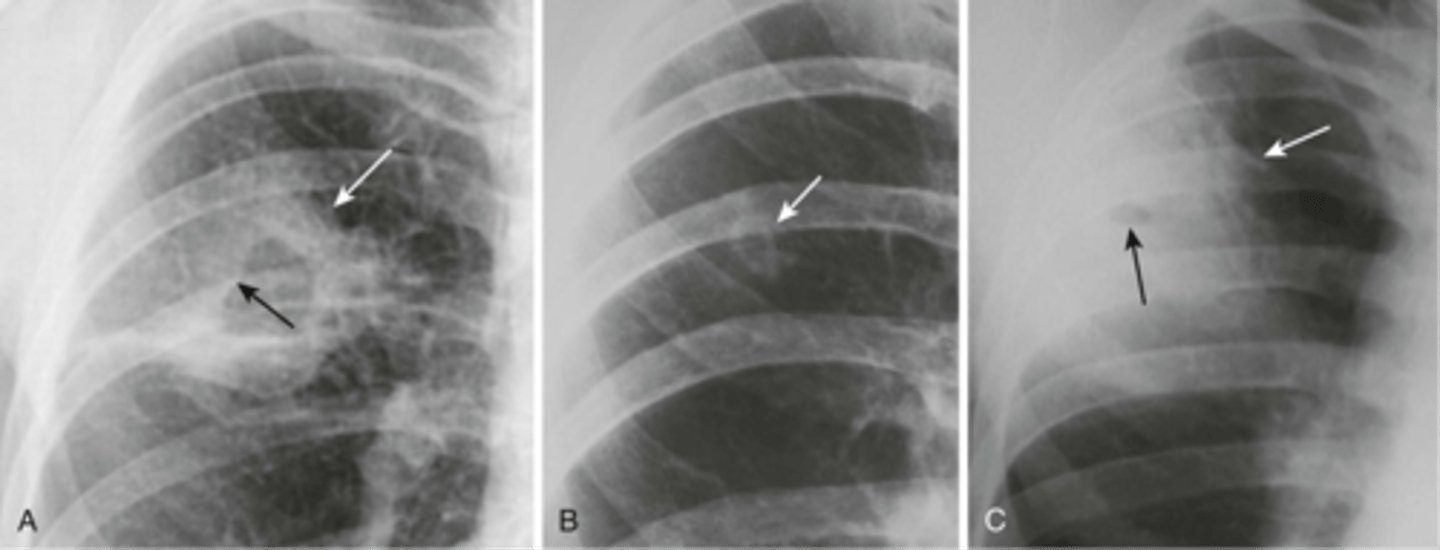

-blunts costophrenic angles

-haze over entire hemithorax (densest at base)

Pleural effusion on an XR

-pleural effusion (fluid will go to the bottom)

-pneumothorax (air will rise to top)

Lateral decubitus view is helpful in diagnosing what